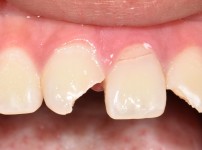

임플란트 재식립 사례

임플란트